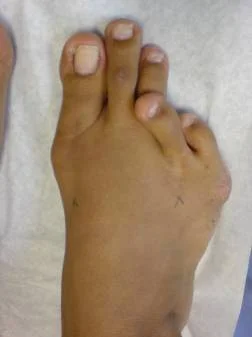

Hallux valgus. Caso clínico:

Paciente femenino de 32 años de edad, quien consulto por dolor en pie derecho, secundario a hallux valgus por metatarso primo varo. Fue intervenida quirúrgicamente con excelentes resultados. Ver más.